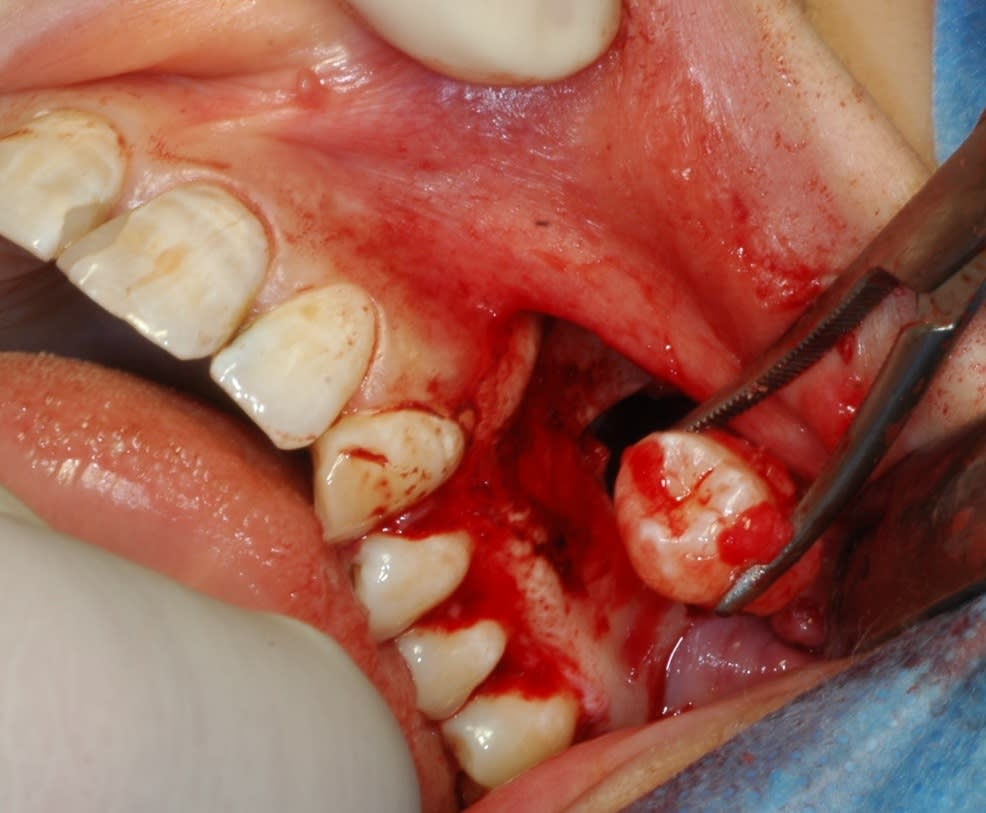

C est un kyste (je pense folliculaire) qui l a projetee au fil du temps dans le sinus.

Le kyste est venu tout seul. Par contre j ai du batailler pour la dent. Elle etait encloisonnee dans septas osseux contre paroi nasale a 90 degres a gauche en entrant :0))

La raison a ete douleur avec ecoulement purulent en distal de la 27. Je pensais remettre a la fin la fenetre osseuse decoupee a Piezo mais ca l a pas fait.